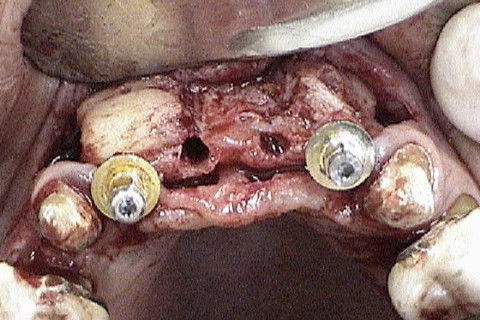

Vista oclusal dos 4 implantes colocados

Preenchimento dos espaços existentes com osso particulado e proteção com membrana de colageno